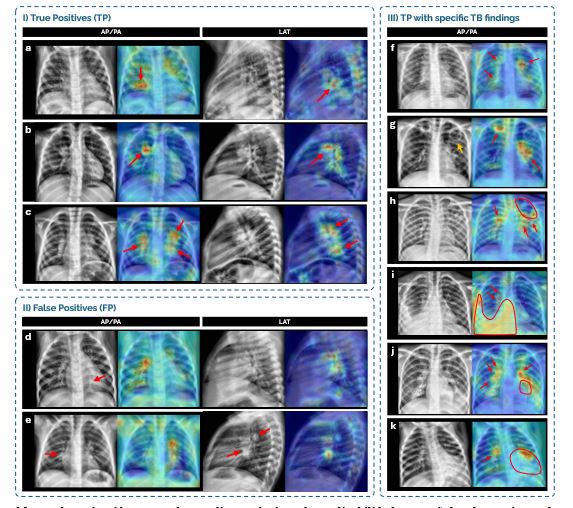

Este sistema integra radiografías de tórax frontales y, si están disponibles, también radiografías laterales con el fin de abordar los retos que supone el diagnóstico de la tuberculosis en niños: síntomas inespecíficos o alteraciones radiológicas más sutiles y variables comparadas con adultos.

Esta investigación demuestra que las radiografías laterales ofrecen información complementaria muy valiosa en lactantes y niños pequeños que las tomas frontales no pueden facilitar. También, que los modelos específicos segmentados por edad superan a los modelos entrenados con todas las edades, debido a las diferencias en el desarrollo y la presentación clínica de la enfermedad entre diferentes grupos de edad.

“Las vistas laterales complementan a la frontal y son especialmente valiosas en lactantes y niños pequeños, ya que ayudan a identificar hallazgos que podrían pasar desapercibidos cuando solo se cuenta con una proyección”, declaró Elisa López Varela, investigadora en ISGlobal durante el estudio.

“El uso de vistas laterales y la adaptación por grupos de edad podrían aumentar la sensibilidad diagnóstica en poblaciones pediátricas, especialmente en lactantes y niños pequeños, donde el diagnóstico resulta más complejo”, añade la pediatra del Gregorio Marañón.